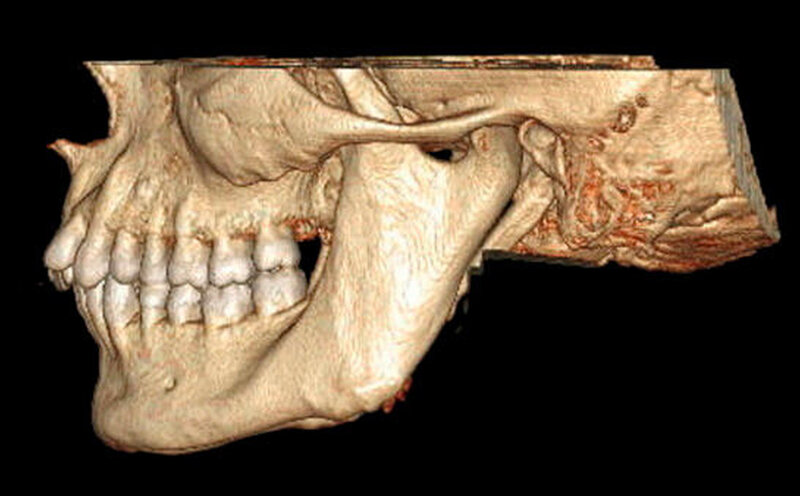

In der erweiterten radiologischen Diagnostik mittels CT zeigten sich symmetrisch angelegte Kiefergelenke beidseits ohne arthrotische Veränderungen oder signifikante Deformierungen. Ein Hinweis auf Luxation ergab sich nicht. In den axialen Schichten stellten sich beide Proc. coronoidei bis hoch in die jeweilige Fossa temporalis dar. In der 3-D-Rekonstruktion imponierten die hyperplastischen Proc. coronoidei beidseits. Diese ragten weit über die Jochbögen hinaus und schränkten dadurch die Mundöffnung ein (Abbildung 3).